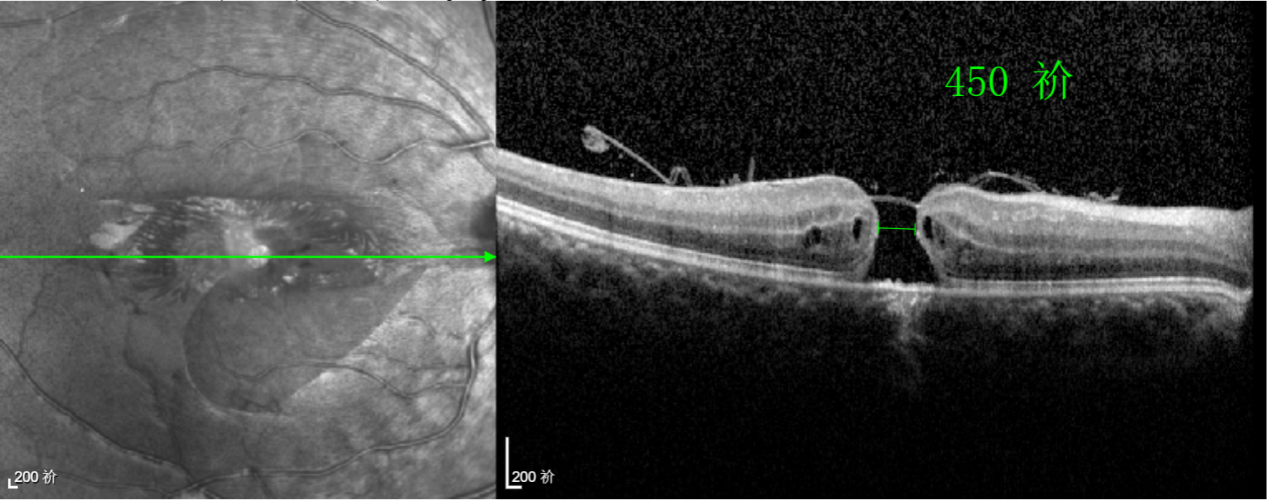

經(jīng)過(guò)詳細(xì)的檢查和評(píng)估,王曉波主任決定采用“內(nèi)界膜翻轉(zhuǎn)覆蓋聯(lián)合粘彈劑固定術(shù)”為誠(chéng)誠(chéng)進(jìn)行治療。

術(shù)中,醫(yī)生精細(xì)剝離黃斑區(qū)的內(nèi)界膜后,并非直接丟棄,而是巧妙地給它翻個(gè)面,讓它變成一塊天然“創(chuàng)可貼”,嚴(yán)密覆蓋在黃斑裂孔的表面。覆蓋的內(nèi)界膜像微型支架一樣撐住裂孔邊緣,防止它擴(kuò)大;同時(shí),這層膜本身含有能促進(jìn)生長(zhǎng)的“養(yǎng)分”,能顯著刺激裂孔周圍的視網(wǎng)膜組織像爬山虎一樣快速生長(zhǎng)、蔓延過(guò)來(lái),最終把裂孔“補(bǔ)”好。

除此之外,利用自體組織覆蓋為黃斑裂孔提供了理想的愈合環(huán)境,裂孔閉合速度顯著快于傳統(tǒng)方法。誠(chéng)誠(chéng)接受手術(shù)24小時(shí)后,檢查可見(jiàn)內(nèi)界膜瓣位置良好;術(shù)后1個(gè)月,黃斑裂孔已經(jīng)閉合,視力恢復(fù)到0.5;術(shù)后兩個(gè)月,視力進(jìn)一步提升到0.7。